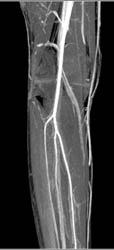

Dislocated Hip in Multiple Views